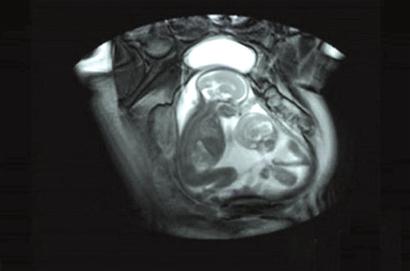

醫療科普:胎兒磁共振成像能做什么? 安全嗎?

產前超聲檢查是胎兒產前首選的影像學檢查方法,但是醫學上的每一種檢查方法都不是萬能的。超聲檢查在一定程度上也存在不足,需要其他檢查方法加以完善,胎兒磁共振成像(MRI)是超聲檢查的一個重要輔助檢查方法,已成為胎兒超聲檢查的重要補充手段。

磁共振成像是斷層成像的一種,它利用磁共振現象從人體中獲得電磁信號,并重建出人體信息。磁共振檢查不存在電離輻射和放射線,因此對胎兒來講是安全的,不會對胎兒發育產生不良影響。

當孕婦過于肥胖、合并子宮肌瘤、羊水過少、子宮畸形、雙胎、多胎、胎兒體位不佳、復雜畸形、孕晚期胎頭入盆、胎頭顱骨骨化等情況時,僅憑超聲檢查所獲得的信息不充分,甚至難以確診。在超聲檢查不能明確診斷,經產科醫師和孕婦充分協商并確認同意后可以行胎兒磁共振檢查。磁共振檢查能彌補超聲的不足,提供額外的診斷信息。尤其在中樞神經系統疾病的診斷上,磁共振明顯優于超聲檢查,因此當產前超聲發現胎兒神經系統異常時,如無充分把握,最好進一步進行磁共振檢查,以提高胎兒神經系統畸形的產前診斷準確率。

目前,胎兒磁共振在產前篩查中得到了越來越多的應用,已成為產前超聲檢查的重要補充手段,并能提供超聲不能發現的額外信息,在預防出生缺陷中體現了越來越重要的價值。